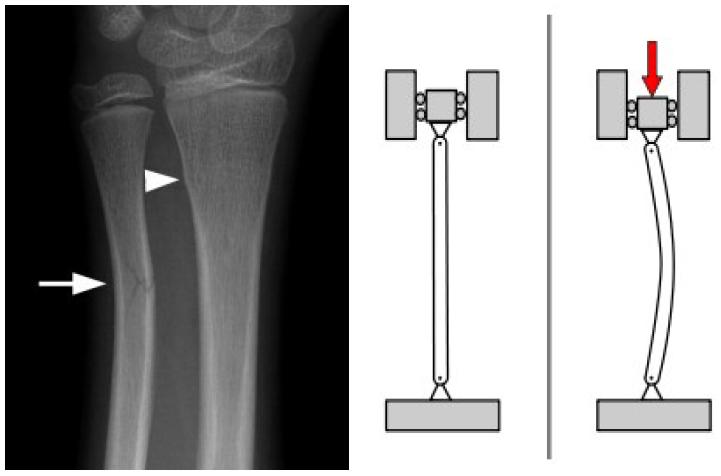

Se consideran dos situaciones, la caída (quiebre por pandeo, compresión o flexión) e impacto en la parte central del hueso (quiebre por flexión).

Si un jugador recibe un impacto en la mitad del hueso y se considera que el pie, debido a la fricción, y el cuerpo, debido a la inercia, son puntos fijos, se genera una carga que flexiona el hueso.